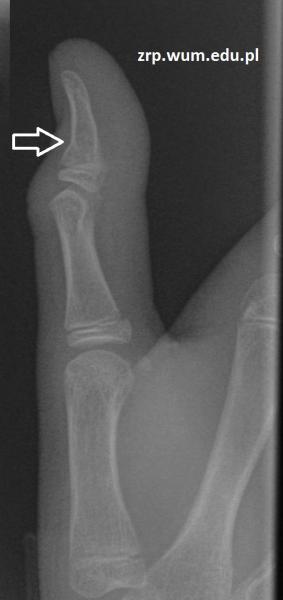

11-letni pacjent po urazie palca I-go ręki prawej

Przypadek 24: 11-letni pacjent po urazie palca I-go ręki prawej.

Rozpoznanie: W badaniu RTG stwierdzono złamanie przynasady bliższej paliczka dystalnego - ugięcie warstwy korowej od strony grzbietowej (strzałka).